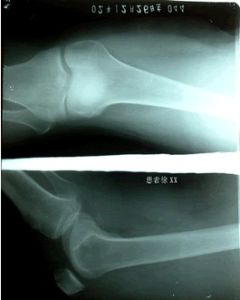

3.X線檢查

照膝關節正、側位及髕骨切線位X線片,早期無異常所見、晚期可因軟骨大部磨損,髕骨與股骨髁部間隙變窄,髕骨和股骨髁部邊緣可有骨質增生。